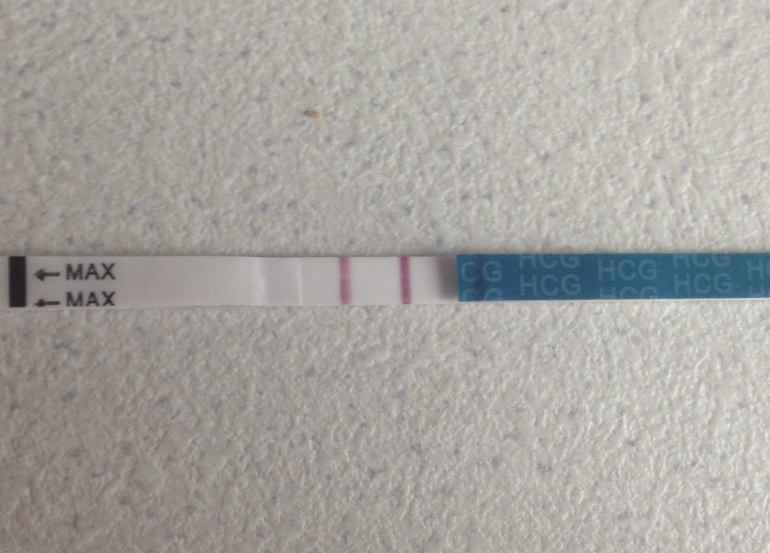

Глаза мои можно было просто впихивать обратно в орбиты

Просто картина маслом.